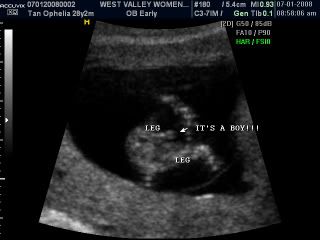

When she was scanning baby legs she asked, would you like to know the gender of the baby, I look and hubby and was like! Yes of course!!! We were really surprised! Cause many mummies can only see their baby's gender at about 4 and a half months! We were like really you can see that already?! And she nods her head...

And the she pointed to us the little pokey thing! Our darling baby is a BOY!!! OMG... Tears started streaming down my face, I didn't know why. I guess its all the excitement and the confirmation of the little life inside me? Life is such a miracle! I mean I told Jason during the first few weeks that I think we are having a boy and OMG its really a boy!!! Jason teared too but wasn't as dramatic as me where I required tissue to wipe all those teardrops off!!!

Anyway our darling boy, i think we shall re nick name you as our little beanie instead, thumbelina is just too girly for you! Here are pictures from the scan! And my little paunch at 12 weeks. Suyi says that I must show them pictures of my paunch!!! Haha... And so here it is!